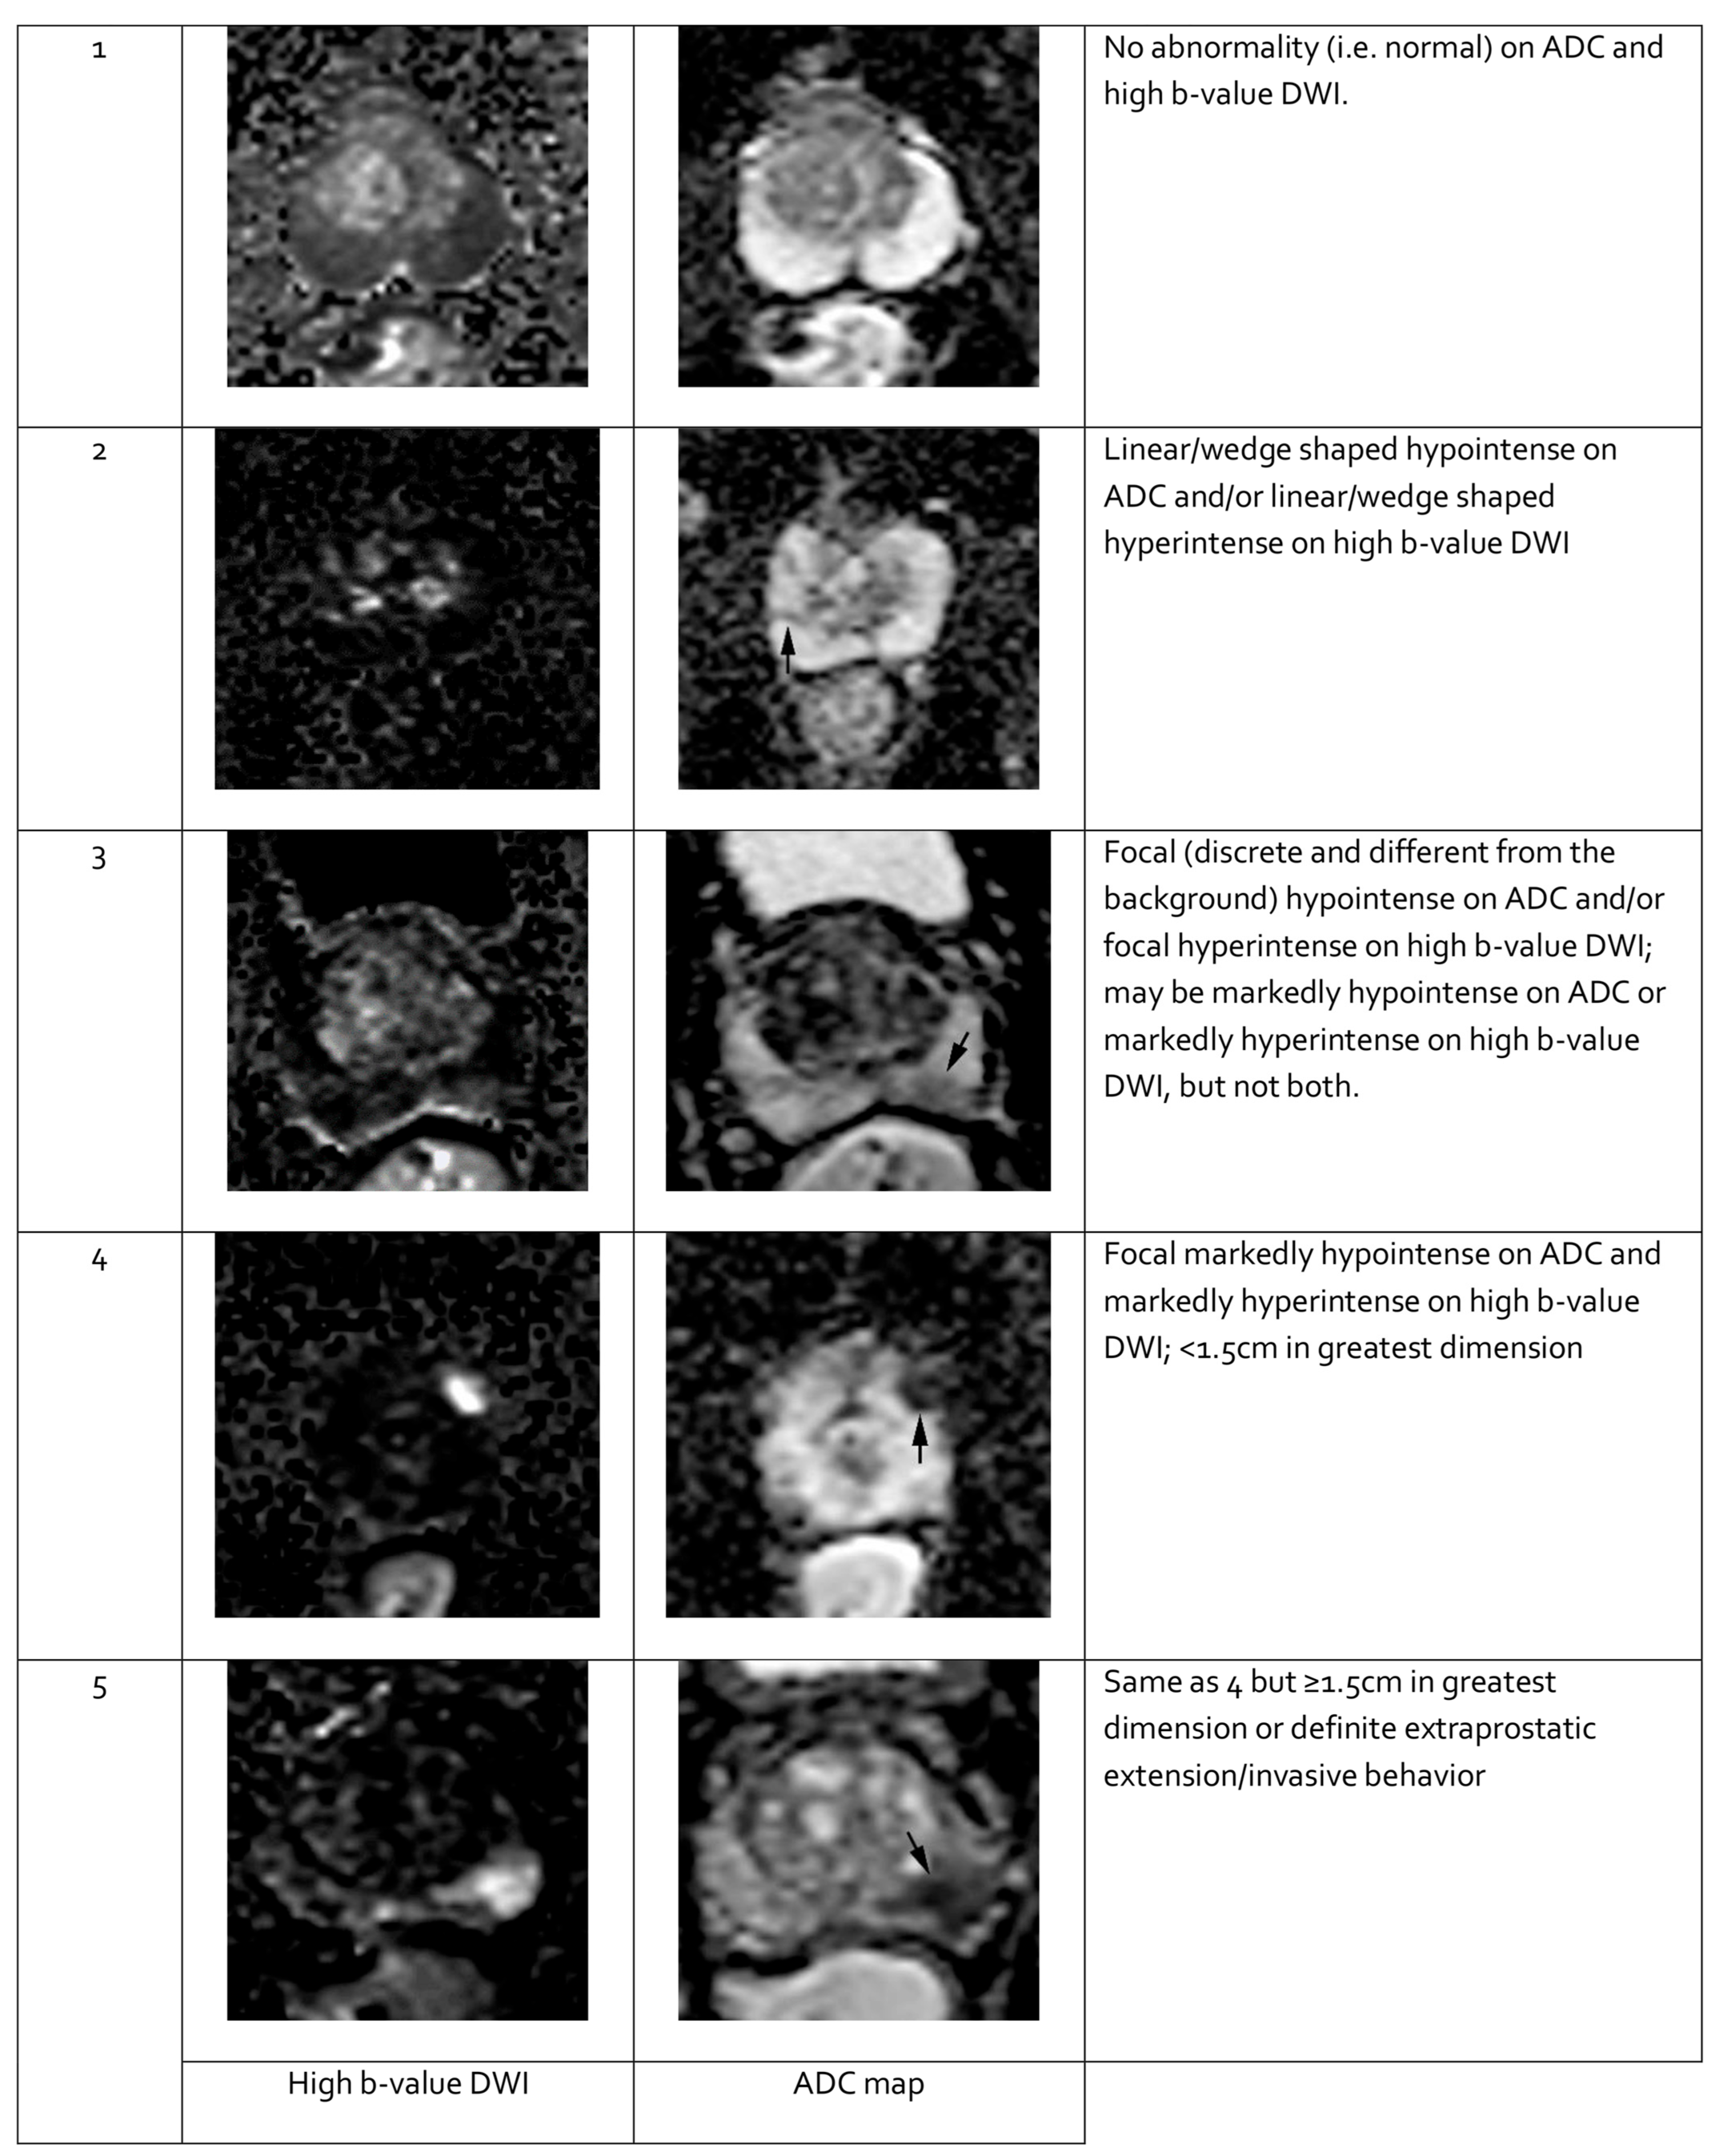

Features seen on mpMRI correlate with the likelihood of malignancy in visualized lesions. To standardize interpretation, the PI-RADS classification was developed. It assigns a score from 1 to 5 to mpMRI-detected lesions, reflecting their likelihood of malignancy [91] (see Table 3). The system is designed to ensure consistent lesion characterization, enhance targeted biopsy precision, and inform treatment decisions. In PI-RADS, each mpMRI sequence is evaluated separately as part of the overall assessment. The overall PI-RADS score is based on the dominant sequence in the affected prostate zone. The final PI-RADS assessment corresponds to the dominant lesion (index lesion) with the highest score within the evaluated prostate zone.

PI-RADS classification should rely exclusively on mpMRI findings, without reference to PSA levels, DRE results, clinical history, or previous treatments. The detection rates of PCa with ISUP grade ≥ 2 based on PI-RADS scores are as follows: 9% (5–13%) for PI-RADS 1–2, 16% (7–27%) for PI-RADS 3, 59% (39–78%) for PI-RADS 4, and 85% (73–94%) for PI-RADS 5 [94].

When evaluating a lesion detected by mpMRI, its anatomical location is critical. T2-weighted images are most informative for lesions in the transition zone, while DWI is dominant for assessing the peripheral zone. Lesion measurements should be performed using the most informative imaging sequence for the specific prostate zone. Representative mpMRI images corresponding to PI-RADS scores are shown in Figure 3 and Figure 4. mpMRI is more effective in detecting clinically significant PCa lesions in the peripheral zone than in the transition zone. Given the growing number of mpMRI examinations, there is a trend toward simplifying protocols by omitting DCE. DCE plays a relatively minor role in primary PCa diagnosis and is associated with potential side effects, longer procedure time, and higher cost [95]. The role of DCE is more significant in the evaluation of local recurrences of cancer after radical treatment [96].

Figure 3.

Representative images of peripheral zone lesions of the prostate gland with various Prostate Imaging—Reporting and Data System (PI-RADS) scores. Reprinted from PI-RADS v2.1 [91] under a Creative Commons Attribution-NoDerivatives (CC BY-ND) 4.0 International License available at https://creativecommons.org/licenses/by-nd/4.0/. ADC: apparent diffusion coefficient; DWI: diffusion-weighted imaging. Black arrows indicate lesions in the respective PI-RADS scores.